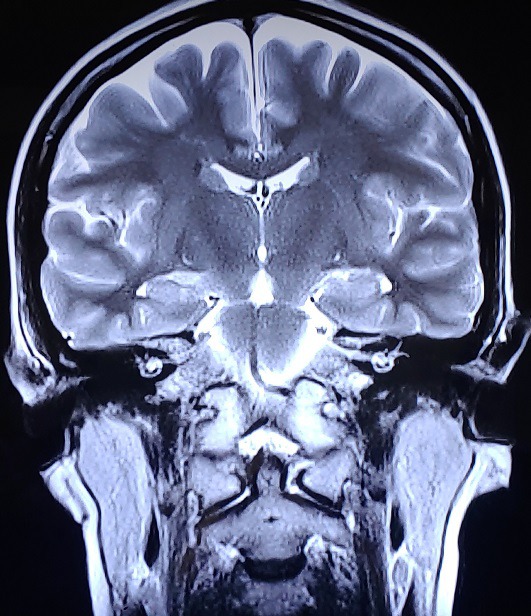

그러고보니 몇 년 전 욕실에서 기절하는 바람에 뇌진탕으로 신경외과에 입원했었는데 그 때 찍은 MRI 에서 약간의 목디스크, 허리디스크가 있다고 했었어요. 근데 그 의사쌤은 ‘요즘 사람들 이정도 다 갖고 사는데 뭘~ 못 걷겠거나 막 심하게 저린거 아니면 괜찮아. 뇌에는 이상없어. 교과서에 실려도 될 정도로 멀쩡하니까 근육쪽만 주사 맞고 물리치료 하자. 내일도 와.’ 라고 하셨습니다..

2017.12.30 경추 회전변위/ 요추 회전변위 / 디스크돌출/ 2020.1.10 역C자 목

당시에는 제가 몇 번 디스크라고 말도 안 해주셔서 몰랐는데 이번 지도사 과정을 배우면서 스스로 알게됐네요. 4-5번 디스크 돌출과 약간 요추후만..으로 보이네요.